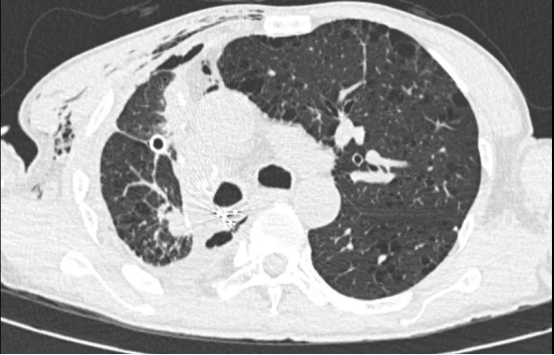

术后影像

术后,患者转入重症一科,在孙万里副主任医师的精细化治疗与护理下,患者接连闯过感染、出血、呼吸功能支持等重重难关。4天后病情趋于稳定,转回胸外二科继续康复。在医护人员的悉心照料下,患者康复出院。